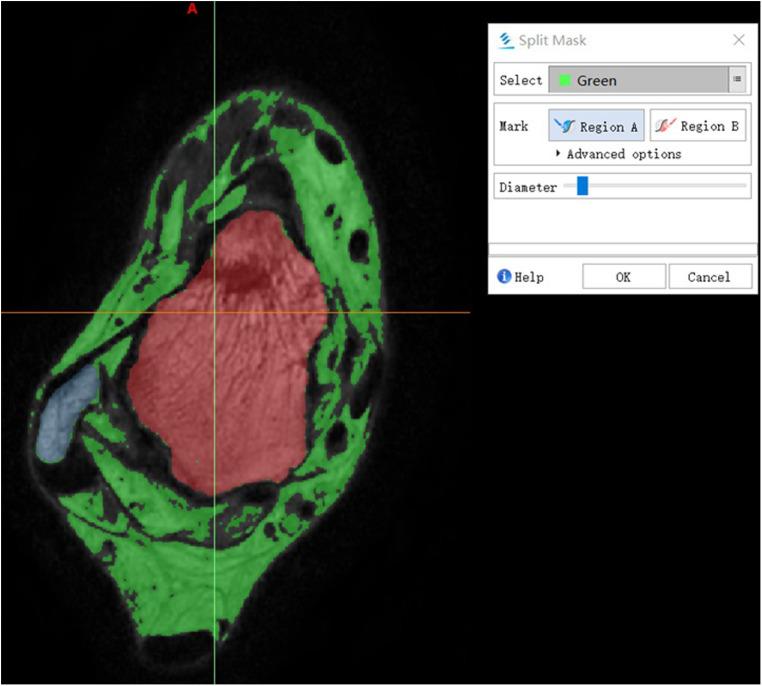

METHODS

A total of 21 healthy asymptomatic volunteers with 30 normally functioning ankles and 13 patients with 18 sprained ankles were studied. MRI scans were divided into two groups: Group 1 (normal ankle) and Group 2 (injured ankle). The data of all 48 cases were exported to Mimics and reconstructed into 3D models. The image quality of all 3D models was evaluated using a 5-point subjective scoring system. The length, width, and thickness of the ATFL were measured in the 3D model in Mimics and compared to the 3D MPR image data.

The image quality score was 4.57 ± 0.32. There was no statistically significant difference between the 3D model and the 3D MPR image of ATFL measurements in both groups ( > 0.05).

We concluded that 3D MRI can be used to reconstruct a 3D model of the ATFL for accurate measurements of the ATFL anatomical structure, which holds potential to improve preoperative planning and intraoperative navigation for young sports medicine doctor, facilitate diagnosis of ATFL injuries and make the decision about the operative method.